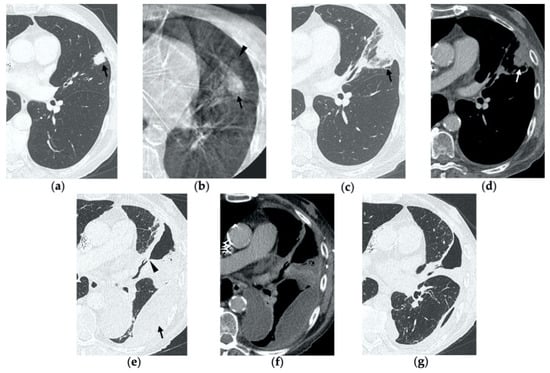

Figure 2. 69-year-old woman with a biopsy-proved NSCLC in the right upper lobe. (a) Pre-treatment axial CT. (b) Cone-beam CT image post-MWA shows GGO (black arrow) among the ablation site. (ce) Axial 1-month follow-up CT shows (c) a large consolidation with well-defined margins, inner hypoattenuating bubbles and a cavitation (black arrow) in communication with a peripheral bronchus (arrowhead); (d) on a different level, central necrotic material is seen within the cavitation (black arrow) (e) with no contrast enhancement (white arrow). (f,g) Axial 6-month follow-up CT images show resolution of the cavitation and decrease in size of the consolidation (black arrow) with no contrast material uptake (white arrow). (h,i) Axial 9-month follow-up CT image shows a linear fibrotic band with no contrast enhancement.

By the first month after MWA, the rim of parenchymal GGO has dissolved in most patients as a result of regressing parenchymal edema, inflammation and hemorrhage, and the ablation site appears as an area of consolidation with a mean diameter still larger than the preablation zone (Figure 3c,d and Figure 4c,d) [21]. It is, therefore, crucial in this phase to measure the area of consolidation by its maximum axial diameter in order to thoroughly compare it during the following phases [7]. The consolidation may demonstrate inner cavitation or a central hypoattenuating area with reduction in contrast material uptake, along with a mild peripheral enhancement layer as an expression of reactive hyperemia, which should present smooth with linear margins (Figure 1c) [7,15]. This phenomenon must be referred to benign periablational enhancement and it should be differentiated from pathological contrast uptake, which is usually more irregular and nodular-shaped [7]. It is, therefore, pivotal to perform CT before and after contrast material administration in order to adequately evaluate the enhancement features of the treated tumor. The ablation site may also show hypoattenuating bubbles or a cavity with thin walls, containing solid tissue with reduced contrast enhancement, necrotic material or air-fluid levels, and a communication between the cavitation and a bronchus may be recognized (Figure 2c–e) [7,16]. The latter being a common finding since the necrotic tissue may be evacuated through a bronchus and it should not be mistaken for rare although possible complications, such as an abscess or a broncho-pleural fistula (BPF). Unlike the normal cavitary changes of the ablation area, an abscess is a rare complication (0.5%) [20] and appears as a cavity with thick walls, irregular internal contours and air-fluid level, and must be suspected when fever and laboratory signs of infection are present [22]. Pleural changes are also common findings, especially in peripheral lesions, including pleural thickening in the region of pleura traversed by the microwave antenna, pleural retraction and effusion [15]. Reactive mediastinal lymphadenopathy often occurs at an early stage, and it should not be considered a sign of tumor progression [7,23].

On CT images obtained at 3-month follow-up, the size of the ablation zone should be the same or still larger than the baseline tumor, although it undergoes further involution compared to the early phase, as during the fibrosis process the wall thickness and the previously depicted cavities progressively decrease (Figure 1d) [7]. The attenuation of the ablated tissue decreases, as there is no more central contrast material uptake in relation to the local necrotic changes, while the peripheral benign enhancement may persist or decrease (Figure 1e). Overall, the size of the ablation area at this stage should become stable along with a decrease in wall thickness [7,8].

After 6 months, the ablation site undergoes further involution and there should not be any inner contrast enhancement, except for the persistent benign periablational area (Figure 2f,g) [7]. The previously mentioned cavities decrease in size and may completely disappear. CT images may show fibrotic scarring without contrast enhancement and mild architectural parenchymal distortion of the surrounding lung (Figure 1f,g) [24]. At this stage, small treated nodules may already show a linear fibrotic evolution on CT images (Figure 2h,i).

During follow-up, there are several evolution patterns of the ablation site, which should promptly raise the suspicion of incomplete ablation or local recurrence.

At all stages of follow-up, the appearance of either central or peripheral nodular or irregular enhancement should be considered as residual or recurrent disease (Figure 4f and Figure 5f), since the ablated area undergoes fibrous transformation, and it should not show contrast enhancement, except for the persisting peripheral safe zone [7,15].